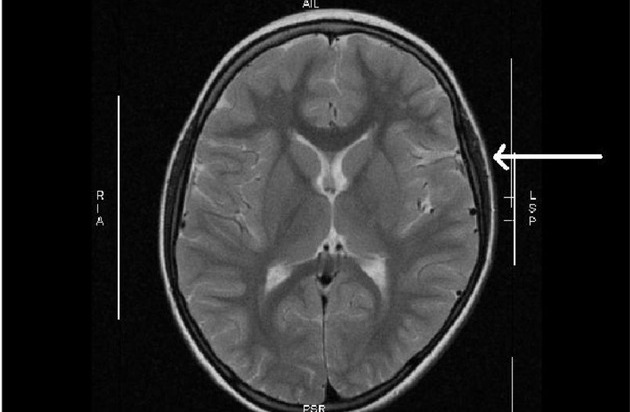

Ein Heilversuch mit Stammzellen bei Schlaganfall nach der Geburt wies den Weg

In einer kürzlich erschienenen Publikation hatte ein kleines Mädchen unter der Geburt einen Schlaganfall mit Halbseitenlähmung erlitten, obwohl es am Termin nach unauffälliger Schwangerschaft der Mutter mit normalen Apgar-Werten bei großem Kopfumfang (> 97. Perzentile) und Anzeichen einer starken Kopfverformung scheinbar gesund geboren worden war. Nach der Magnetresonanz-Tomographie des Schädels (MRT), die einen wegweisenden Befund ergab, wurde die Stammzellbehandlung aus Nabelschnurblut erfolgreich durchgeführt. "Zu unserer Überraschung war die Druckstelle am Gehirn durch die mechanische Kompression 5 Jahre nach der Geburt des Mädchens immer noch sichtbar", erinnert sich Prof. Arne Jensen. "Wir haben daraufhin unsere Datenbank gezielt durchsucht und festgestellt, dass bei Kombination von großem kindlichen Kopfumfang mit protrahierter Geburt oder Geburtsstillstand ein hohes Risiko für eine Hirnschädigung in der weißen Substanz besteht."